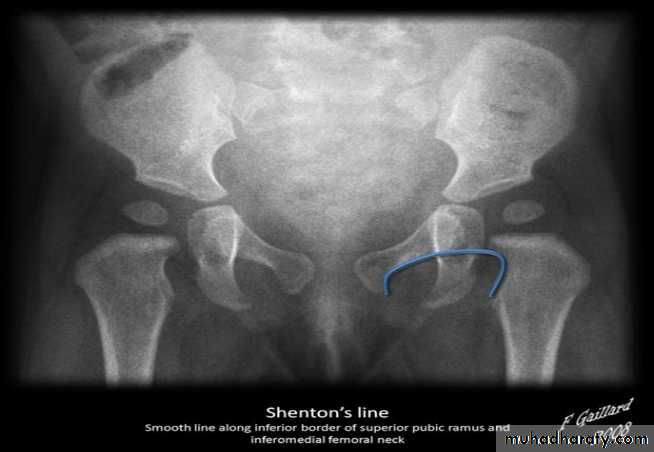

Who can you do Von Rosen view

At 3-6 months :abduction of the thigh 45 degree and internal rotation

Shenton line is drawn along the inferior border of the superior pubic ramus and should continue laterally along the infero medial aspect of the proximal femur as a smooth line. If there is supero lateral migration of the proximal femur due to DDH then this line will be discontinuousPerkin line is drawn intersecting the lateral most aspect of the acetabuler roof & iliac creast

Q…CDH occurs most commonly in ????(70%) in the left hip . Bilateral involvement is seen in 5%

Q…By simple diagram draw pelvis with lines (shenton’s & Perkins line)